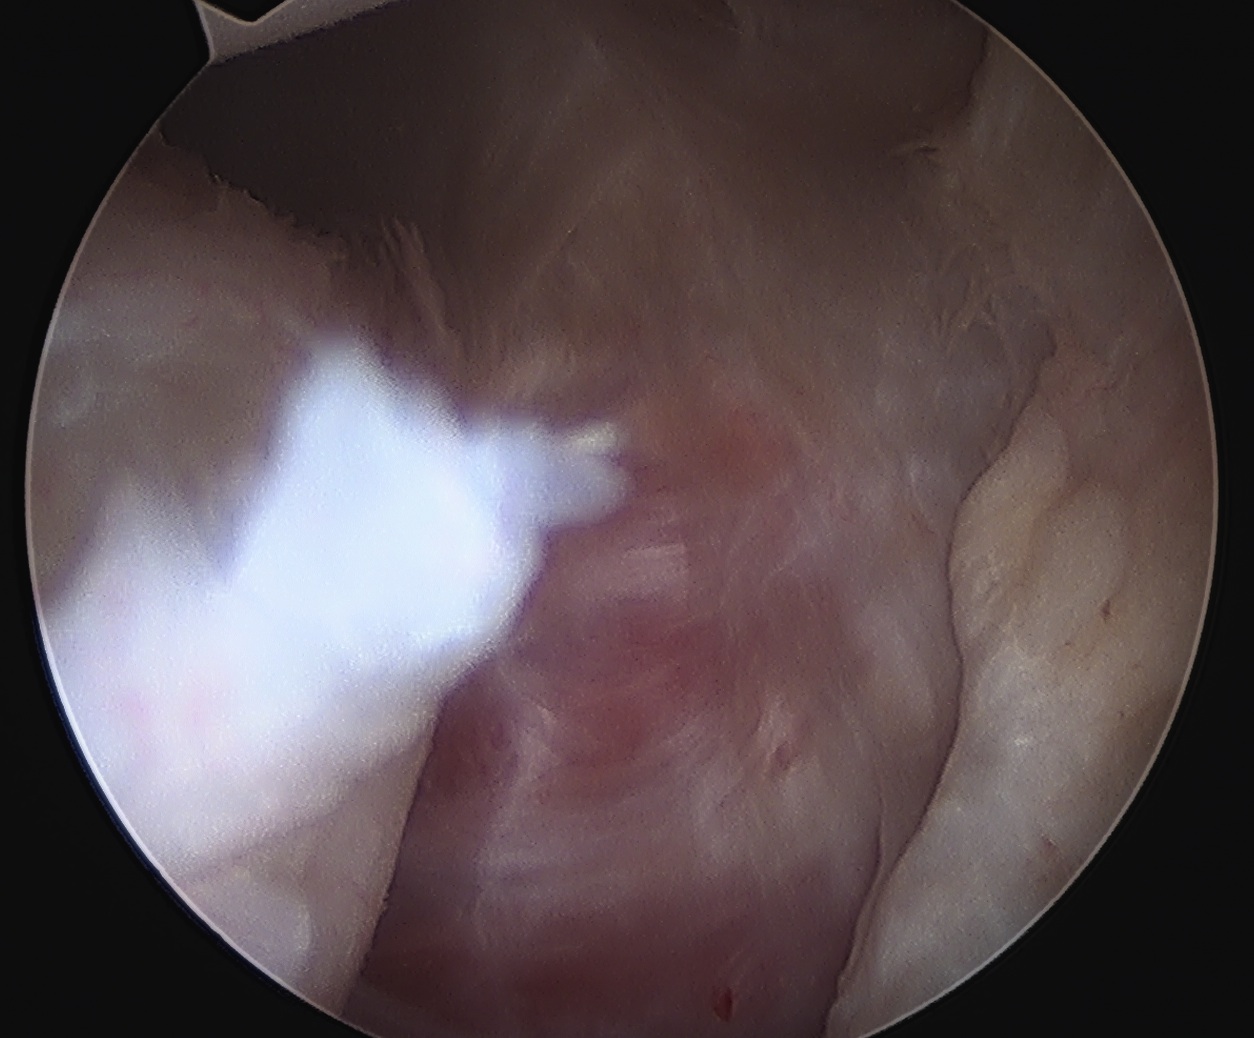

Arthroscopy

Anterior labral tears

Anterior capsule tears